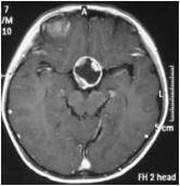

入院后行CT、MR检查,显示:鞍区及鞍上较大占位病变,考虑颅咽管瘤。遂于2010-08-11在全麻下行“鞍区及鞍上颅咽管瘤切除术”,术后病理:造釉细胞型颅咽管瘤。于2011-01-04开始给予三维适形放疗,总结量5040cGy/28F。放疗后,患者定期回院复查肿瘤复发征象。

2010年8月 术前